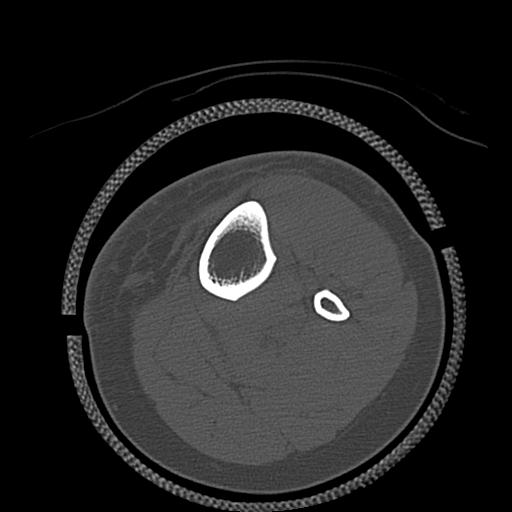

110211 1/6 1/8 左前腕 4R 15歳男性 橈骨骨幹部骨折